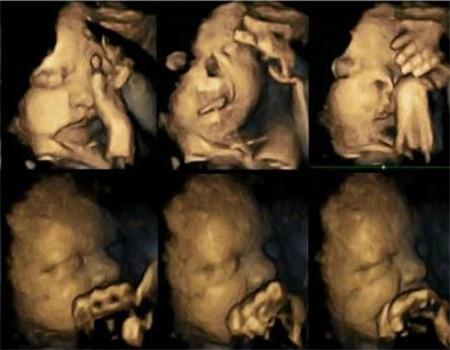

吸烟对胎儿究竟有什么伤害,当看到宝宝在四维彩超下的惨状,请妈妈“口下留情”吧!

并且在20个孕妇中的研究发现,其中4个人平均每天抽4根烟,检测的周数是在他们怀孕第24、28、32、36周。专家发现,这些孕妇的婴儿,会跟频繁的摸自己的脸,动自己的嘴巴,且表情痛苦。